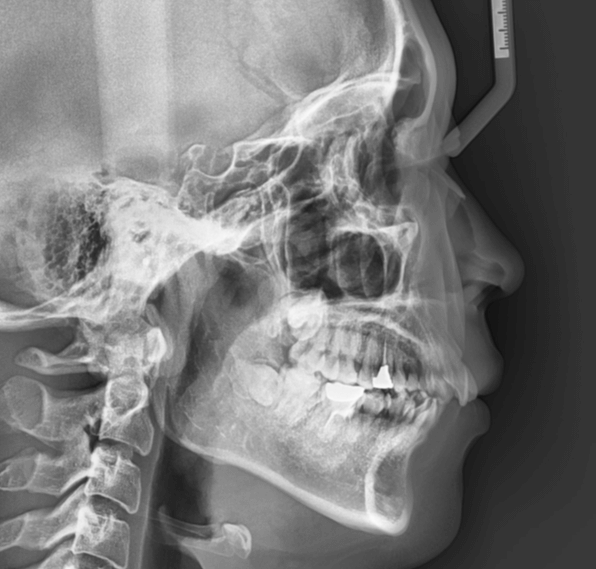

| 年齢・性別 | 25歳女性 |

|---|---|

| 主訴 | 前歯の歯並びの乱れ(叢生)を気にされて来院された。咬み合わせや審美的な改善を希望されていました。 |

| 治療期間・回数 | 4年5ヶ月・30回 |

| 費用 | 1100,000円(税別) |